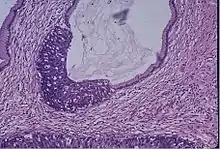

Cervical cancer

Cervical screening by the Pap test or other methods is highly effective at detecting and preventing cervical cancer, although there is a serious risk of overtreatment in young women up to the age of 20 or beyond, who are prone to have many abnormal cells which clear up naturally.[24] There is a considerable range in the recommended age at which to begin screening around the world. According to the 2010 European guidelines for cervical cancer screening, the age at which to commence screening ranges between 20 and 30 years of age, "but preferentially not before age 25 or 30 years", depending on the burden of the disease in the population and the available resources.[25]